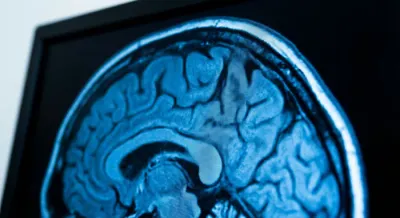

Imagerie et analyses biologiques

Comprendre les termes d'un compte rendu de radiographie ou d'une analyse sanguine peut sembler intimidant. Entre les taux de cholestérol, les marqueurs inflammatoires et les clichés d'IRM, il est facile de s'y perdre. Cette section explore les fondamentaux de l'imagerie médicale et des bilans biologiques pour vous aider à mieux appréhender vos examens. Nous levons le voile sur les protocoles courants et la signification réelle des chiffres. Une analyse bien comprise est une source de stress en moins dans votre parcours de soin.

IRM lombaire anormal : comprendre les résultats et suites

Recevoir un compte-rendu médical rempli de termes techniques génère souvent une anxiété immédiate. Vous n'êtes pas seul face à ce jargon complexe. Souvent, la lecture du rapport révèle des anomalies qui semblent effrayantes, mais qui ne sont pas forcément synonymes de chirurgie ou de handicap futur. Apprendre à décrypter les signaux de votre organisme est la première étape pour mieux gérer son anxiété face à l'imagerie. Cet article vous aide à décrypter un résultat d'IRM lombaire anormal, à comprendre la gravité réelle des lésions et à envisager la suite avec lucidité. Nous allons traduire le langage radiologique en explications claires pour vous permettre de reprendre le contrôle sur votre santé dorsale, car une image inquiétante ne condamne pas nécessairement votre dos à l'immobilité.